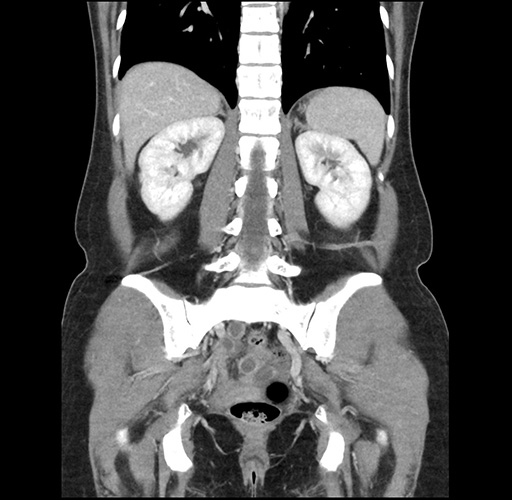

Imaging Analysis

Look through the patient's CT scan to identify any areas of concern for the necessary procedure.

Based on your CT findings, which issue(s) would give reason for "planned slowing down moment(s)" in this case?

Considering a standard left lateral sectionectomy procedure, what step(s) of the operation would you do differently in this case ?